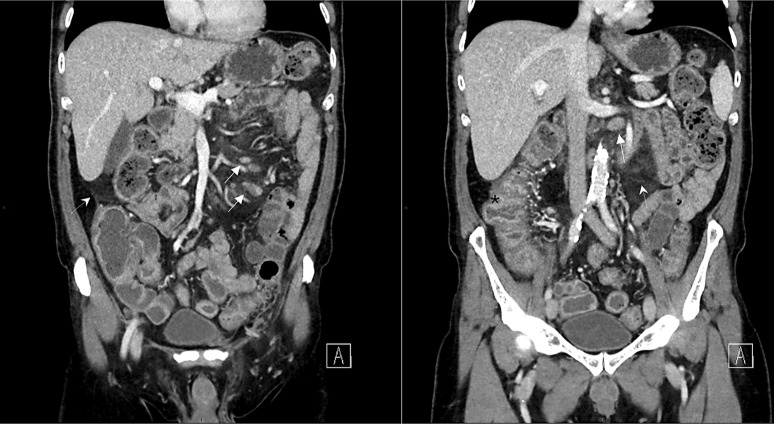

Case presentation: A 69-year-old male with stage IV follicular lymphoma, treated with obinutuzumab-CHOP and subsequent obinutuzumab maintenance therapy, developed non-bloody diarrhea after his third maintenance dose. Endoscopic and histological findings mimicked Crohn's disease, leading to a diagnosis of obinutuzumab-induced pancolitis. Obinutuzumab was discontinued, and the patient was transitioned to infliximab therapy, leading to partial improvement.

Conclusion: This case demonstrates a severe instance of obinutuzumab-induced pancolitis with IBD-like features, emphasizing the need for clinicians to consider drug-induced etiologies in patients presenting with new gastrointestinal symptoms during obinutuzumab therapy. Timely diagnosis and a multidisciplinary approach are crucial for effective management. Further reports are needed to better understand the full spectrum of gastrointestinal toxicity associated with obinutuzumab and guide future treatment.